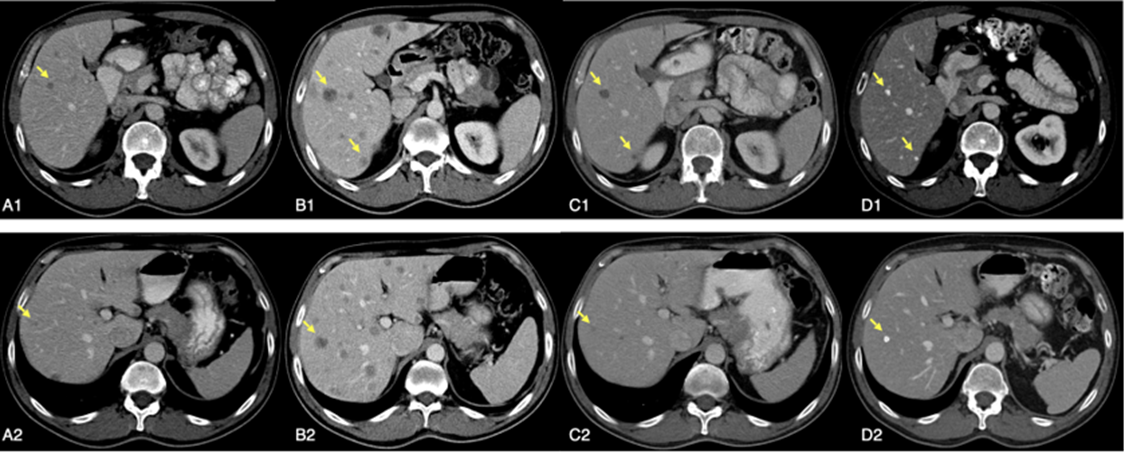

A man in his 50s with a diagnosis of localized melanoma of the nasal mucosa, treated by excision of the lesion and partial maxillary surgery, was referred to our service one month later due to hepatic progression detected on computed tomography (CT) (Figure. Panel A1-2) performed as a result of mild abdominal symptoms during adjuvant radiotherapy.

A CT scan performed after three cycles of treatment, revealed a clear increase in the size and number of liver lesions (Figure. Panel B1-2) and multiple new lung nodules. Liver function tests were normal. According to the protocol, the fourth cycle was administered as scheduled, and a new CT scan was planned six weeks later, during nivolumab monotherapy.

A month and a half later, CT scan showed a partial response (Figure. Panel C1-2). At the same time, the patient began to develop cutaneous vitiligo, which spread over a few months to the upper trunk and generalized to the whole body.

Figure 1: Sequence evolution of two CT scan slices of some hepatic metastases.

A1-2; basal imahe. B1-2; pseudoprogression afret three cycles of treatment. C1-2; partial response. D1-2; calcification of liver metastases 87 months after stopping treatment.

A PET/CT at the end of 2016, confirmed a complete metabolic response of all lesions. He continued treatment with good tolerability and radiological stability until completing 2 more years of treatment, about 4 years from the beginning, when nivolumab treatment was stopped. Subsequent CT studies during the follow-up were reported as “stable residual lesions of indeterminate significance”, undetectable by PET.

Early 2024, the patient maintains a fully active life in excellent state of health, and the CT scan report described and unchanged residual calcified hepatic punctiform nodules (Figure. Panel D1-2 and Video.) with no other evidence of residual melanoma, 87 months after stopping treatment.